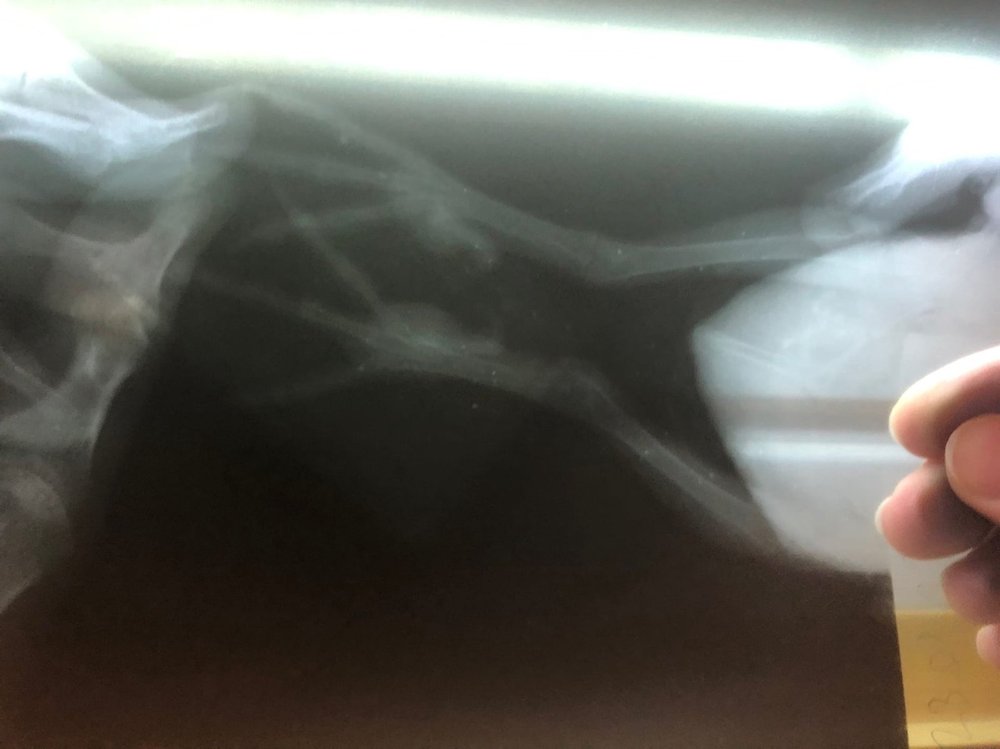

Juan_Esteban_Vazquez Опубликовано 14 марта, 2022 Автор #90 Опубликовано 14 марта, 2022 Всем привет! Хотел спросить стоит ли этих наростов (думаю, что именно они подагрические тофусы) вскрыть или не надо? И еще чем можно заменить Линкомицин (смесь №2)? У нас в продаже сейчас нигде его нет (одна ампула была у нас в доме. Сейчас говорят, что его нет в продаже уже больше 1,5 года). Лапки выглядят сейчас так: Скрытый текст

OFA Опубликовано 25 февраля, 2022 #89 Опубликовано 25 февраля, 2022 @Juan_Esteban_Vazquez вот так выглядят тофусы подагрические и да, они вскрываются, как гнойники https://www.mybirds.ru/forums/topic/165789-opuholi-gnoyniki-na-lape-u-volnistika/?do=findComment&comment=2180868 Почитайте ниже сообщения с фото комментарии Зоси 1